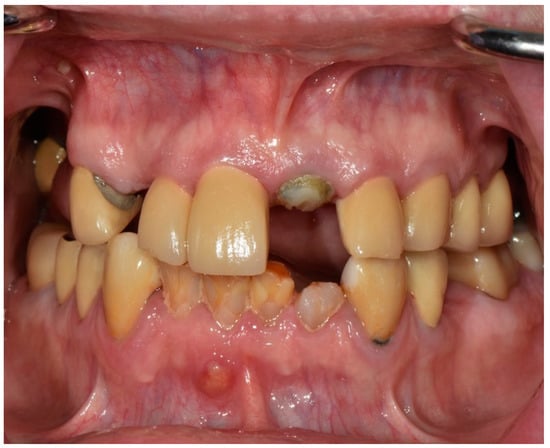

Full-Mouth Rehabilitation of a Patient with Sjogren’s Syndrome with Maxillary Titanium-Zirconia and Mandibular Monolithic Zirconia Implant Prostheses Fabricated with CAD/CAM Technology: A Clinical Report

2. Materials and Methods

3. Results